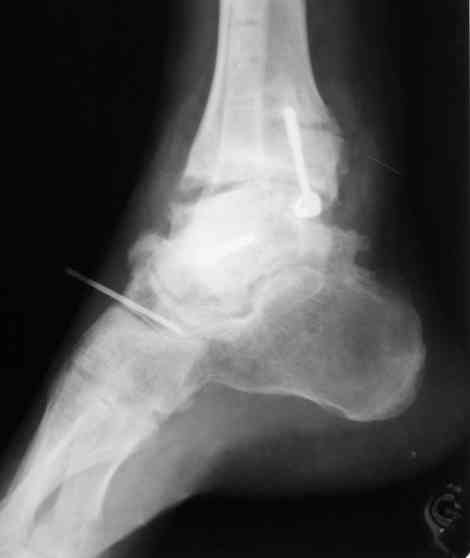

В Вашей ситуации мы произвели открытую репозицию и фиксацию металлоконструкциями. Все зажило первично, посттравматического дефартроза избежать не удалось. Пациент от артродезирующих операций в отдаленном периоде отказался.